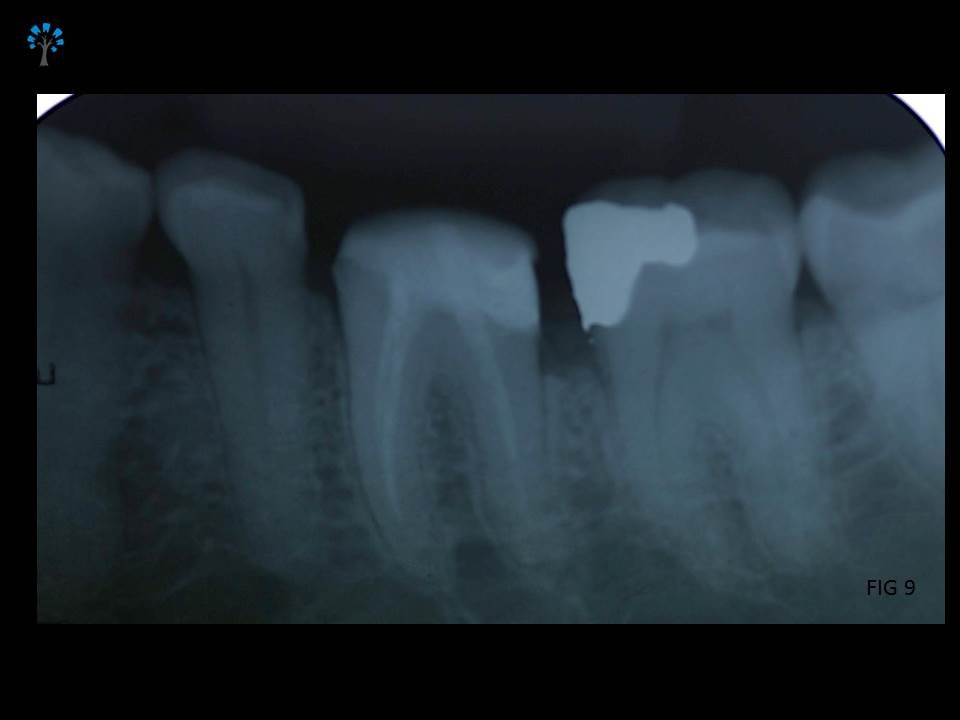

Given the medical status of the patient and based on certain existing favorable anatomic features with diagnosis from the Intra oral xray (Fig 2), we decided to retain the tooth and restore it.

Fiber Post (IVOCLAR*) was placed and the core structure was built.(Fig 7 – 9)